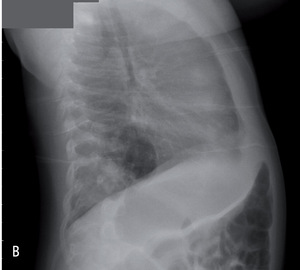

Rycina 2. Zdjęcia przeglądowe tylno-przednie (A) i boczne (B) dwutygodniowej dziewczynki z sekwestracją zewnątrzpłatową lewego płuca.

Rycina 3. Zdjęcia przeglądowe tylno-przednie (A) i boczne (B) trzymiesięcznego chłopca z sekwestracją wewnątrzpłatową dolnego płata prawego.